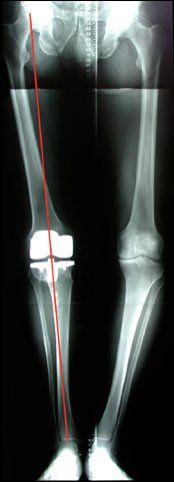

On recherche essentiellement à l’examen : une désaxation de la jambe constitutionnelle mais aussi liée à l’usure du cartilage, une perte de mobilité en particulier de l’extension, une perte musculaire (amyotrophie) qui traduit une sous utilisation du genou. On détermine également un retentissement du genou atteint sur le dos, la hanche ou la cheville.

L’étude des radiographies analyse la déformation réelle, les articulations sus et sou jacente et le degré d’usure. Il est important de préciser que l’indication de prothèse se pose dans la majorité des cas devant un bilan radiologique standard. Une IRM ne doit donc pas être le principal examen.

Désaxation et perte d’extension